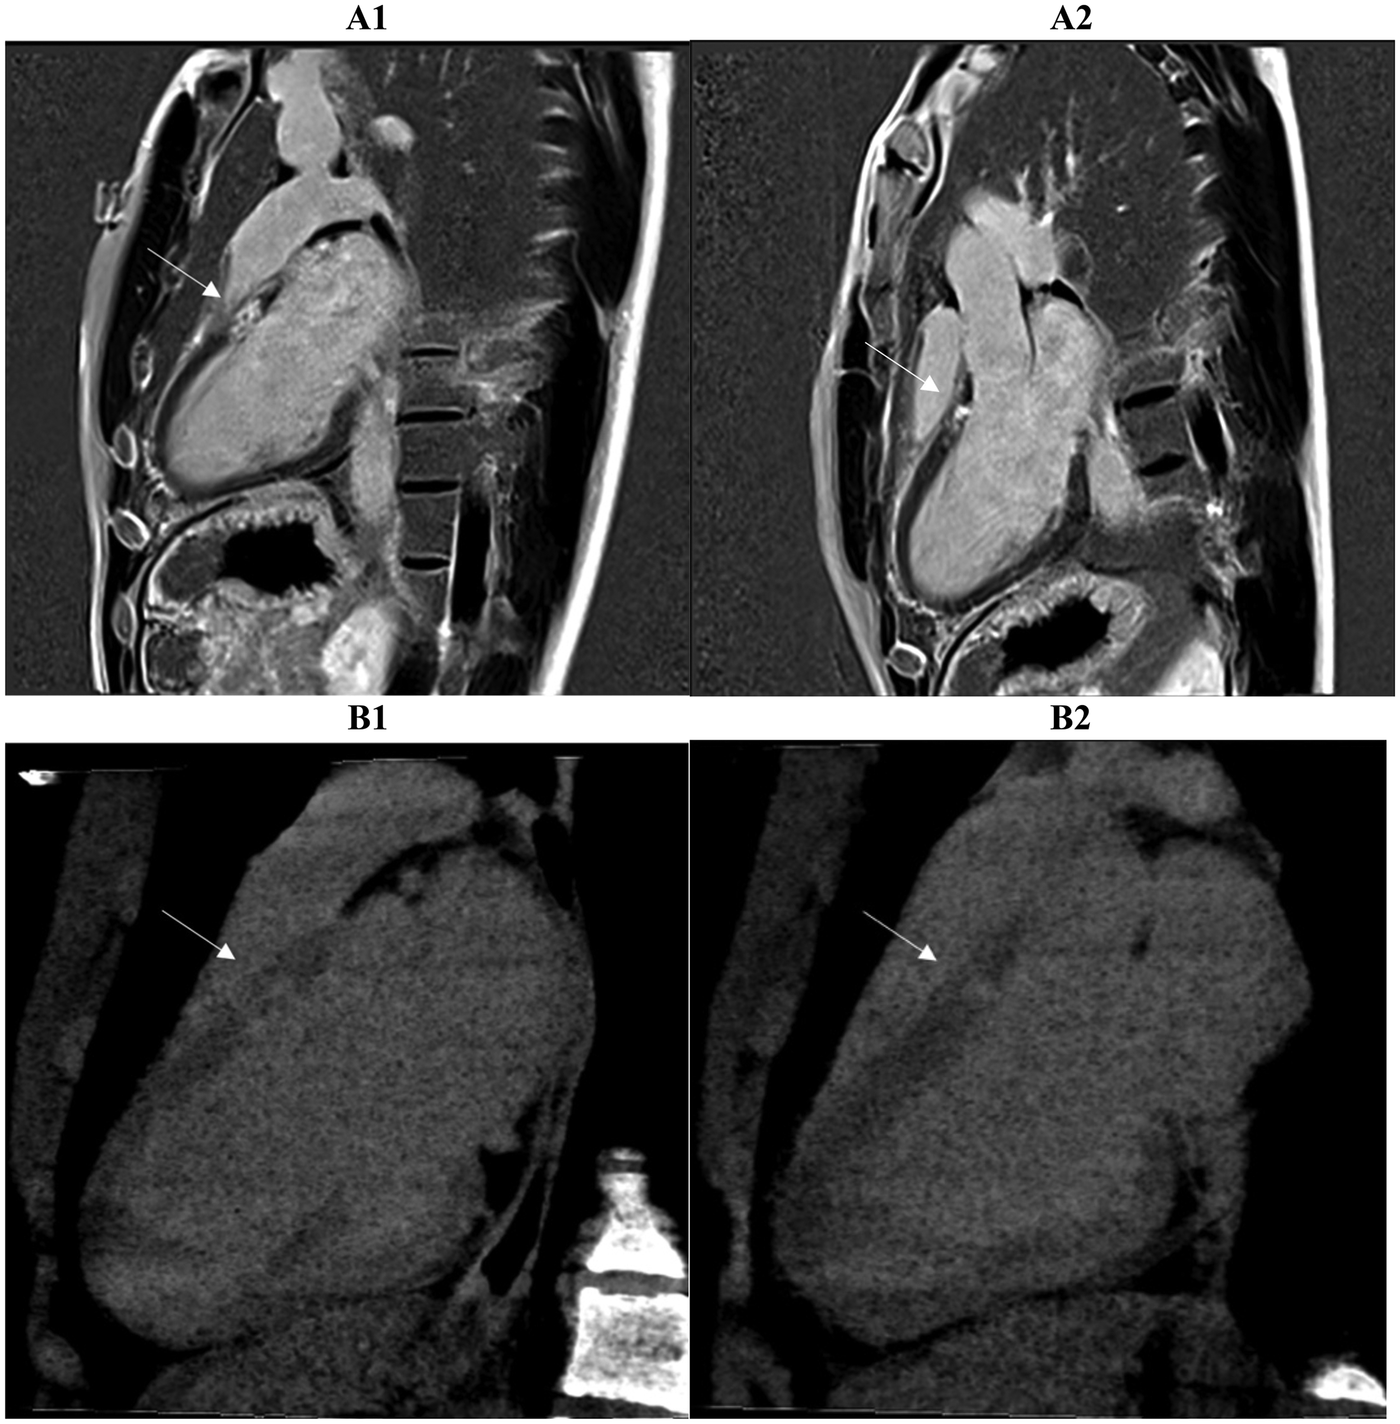

Figure 3

Two myocardial tissue characterization slices on CMR (A1, A2) and CCTA (B1, B2) in the same patient diagnosed with myocarditis at discharge are shown. Both the long-axis four-chamber and three-chamber views reveal intramural or sub-epicardial enhancement (arrows) with 80% segmental concordance between the imaging techniques, based on matching presence or absence of enhancement in corresponding myocardial regions. CMR, cardiac magnetic resonance; CCTA, coronary computed tomography angiography.